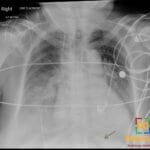

- Radiology Cases: Images with a to-the-point discussion highlighting the specific diagnostic criteria.

Latest Radiology Cases